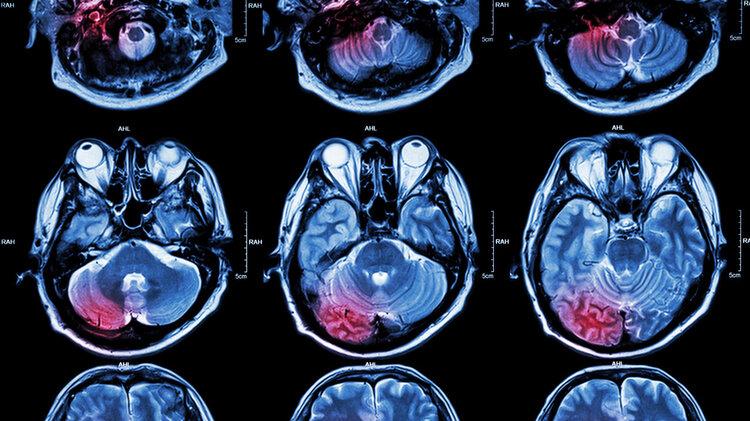

(图源视觉中国)

【连续发生!来杭打工第一天,25岁壮小伙被送进抢救室!医生叹气:真别再“作”了...】几次的心电图结果一致 , 这种心电图 , 在心血管医生圈里有个行话 , 叫“红旗飘飘” , 出现这种情况 , 就是很典型的急性心肌梗死 。

检查结果出来 , 郑娉娉迟疑了一会 , 心电图提示ST段抬高 。 这意味着小夏极可能是冠心病中最危急的心肌梗死 , 也是心血管内科里最危急、最要命的疾病之一 。 这么年轻 , 就发生这么严重的心肌梗死 , 这让见过颇多世面的医生们也大呼意外 。